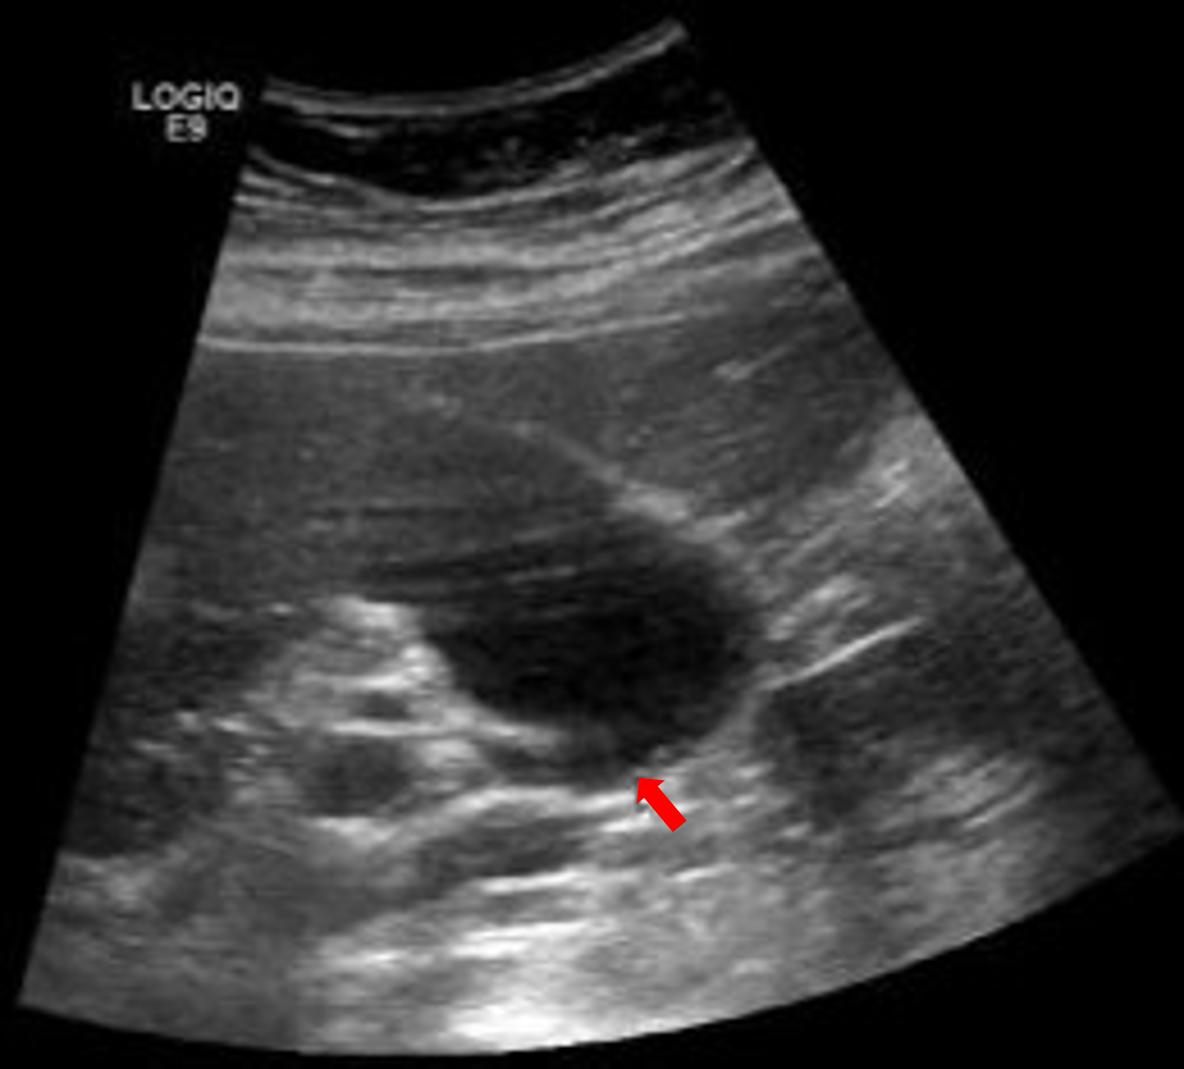

图五,这个红笔圈出的是餐后的胆囊,胆汁排出了一部分,相比之下,这个胆囊壁的褶皱之间有没有息肉和结石,就不好说了。